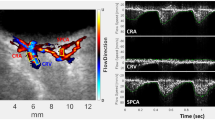

Image analysis

The XyCAM image analysis software provides the user with analytical tools to choose specific regions of interest, and select time-intervals over which the blood flow waveform will be analyzed. Detailed reports contain various retinal blood flow metrics associated with the user-chosen regions and time windows. To examine the retinal blood flow metrics at the optic nerve head, as a theoretical best indicator of total ocular blood flow, the outline of the optic nerve was drawn using a free-form region-selection tool while assisted by fundoscopic image overlay (Fig. 1). To compensate for any motion artifact, the analysis software registers all frames to a single image frame prior to computation of BFV indices27. The software also automatically detects peaks and dips in the blood flow waveform that can be manually adjusted if needed to define cardiac cycles. Time intervals chosen for analysis comprised of at least 2 continuous cardiac cycles, and the following 3 blood flow metrics were extracted and statistically analyzed: peak, mean, and dip BFV index. Final analysis was limited to the mean BFV index because results did not differ among peak, mean, and dip velocity indices.